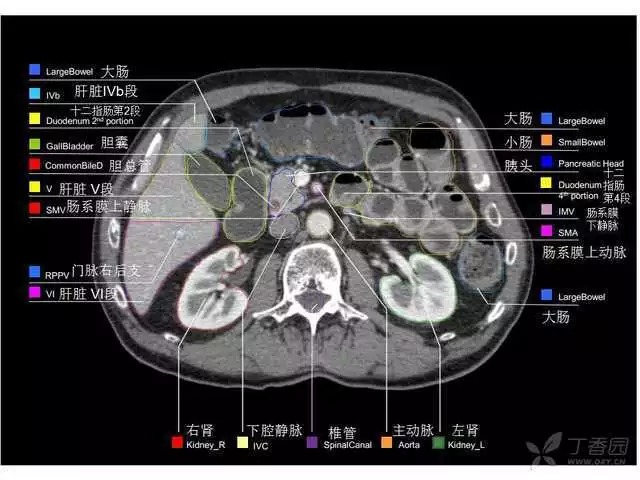

腹部肝脏高清CT断层的图谱

全腹部高清CT图谱,淋巴结彩色图谱,血管解剖图谱大汇总!

肝段,肝内管道的分布规律